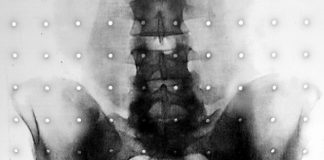

Sakroilijakalni zglob dosta često uzrokuje bol u lumbalnom dijelu leđa. Oko 80 posto odraslih pati od boli u donjem dijelu leđa u nekom periodu...